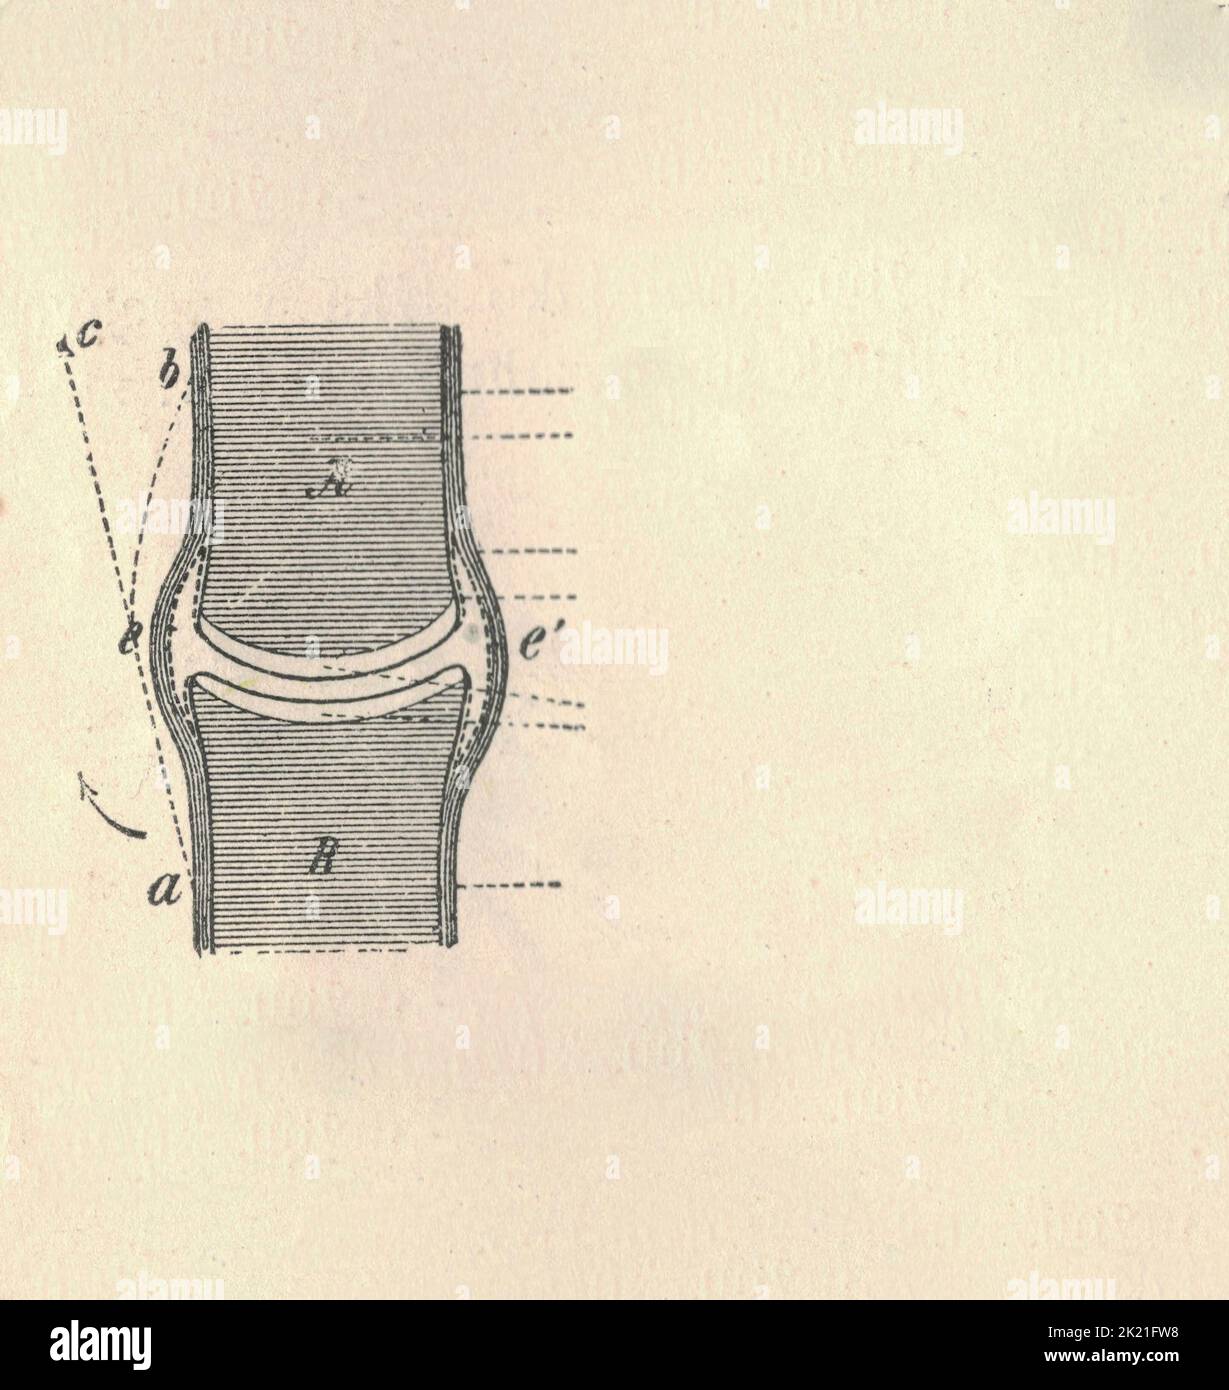

Anatomie articulaire avec des lettres de légende (os, muscles). Illustrations vintage. Y compris la légende des figures. Banque D'Imageshttps://www.alamyimages.fr/image-license-details/?v=1https://www.alamyimages.fr/anatomie-articulaire-avec-des-lettres-de-legende-os-muscles-illustrations-vintage-y-compris-la-legende-des-figures-image483154036.html

Anatomie articulaire avec des lettres de légende (os, muscles). Illustrations vintage. Y compris la légende des figures. Banque D'Imageshttps://www.alamyimages.fr/image-license-details/?v=1https://www.alamyimages.fr/anatomie-articulaire-avec-des-lettres-de-legende-os-muscles-illustrations-vintage-y-compris-la-legende-des-figures-image483154036.htmlRF2K21FW8–Anatomie articulaire avec des lettres de légende (os, muscles). Illustrations vintage. Y compris la légende des figures.